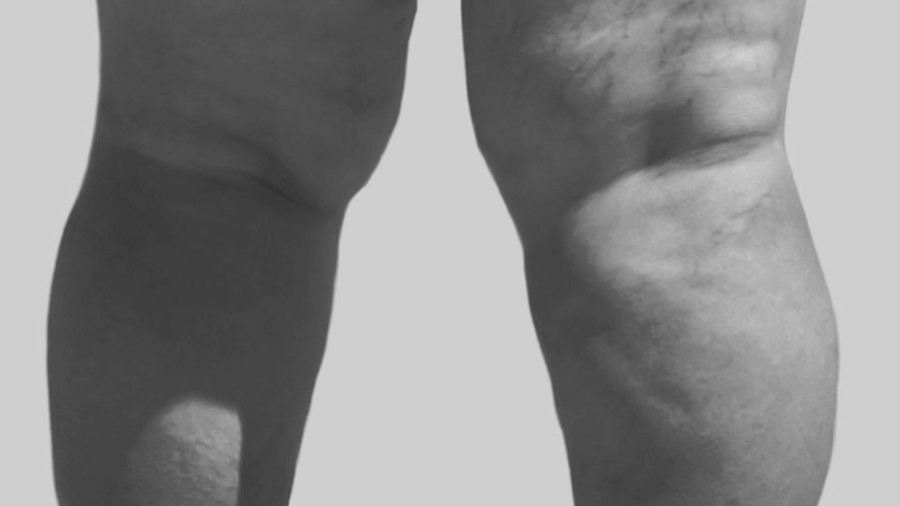

Lipedema is a chronic condition characterised by abnormal fat accumulation usually in the lower and upper extremities, often resulting in pain, discomfort, and significant psychological distress. The condition disproportionately affects women and is commonly misdiagnosed, leading many patients to struggle with the symptoms for years. Fortunately, advances in lipedema treatment, particularly lipedema reduction surgery, have proven to be an effective way to alleviate both the physical and emotional burdens of this condition.

One of the primary reasons individuals seek lipedema surgery is the physical relief it offers. Lipedema often leads to discomfort and pain due to the excessive accumulation of fat cells in the extremities. As these cells build up, they can cause tenderness, heaviness, and an overall sense of discomfort. The surgical reduction of this fat can significantly reduce these symptoms.

One of the more immediate, functional advantages of lipedema reduction surgery is the ability to wear clothing with greater ease and confidence. Many lipedema patients struggle with finding clothes that fit properly due to the disproportionate distribution of fat, particularly in the hips, thighs, and calves.